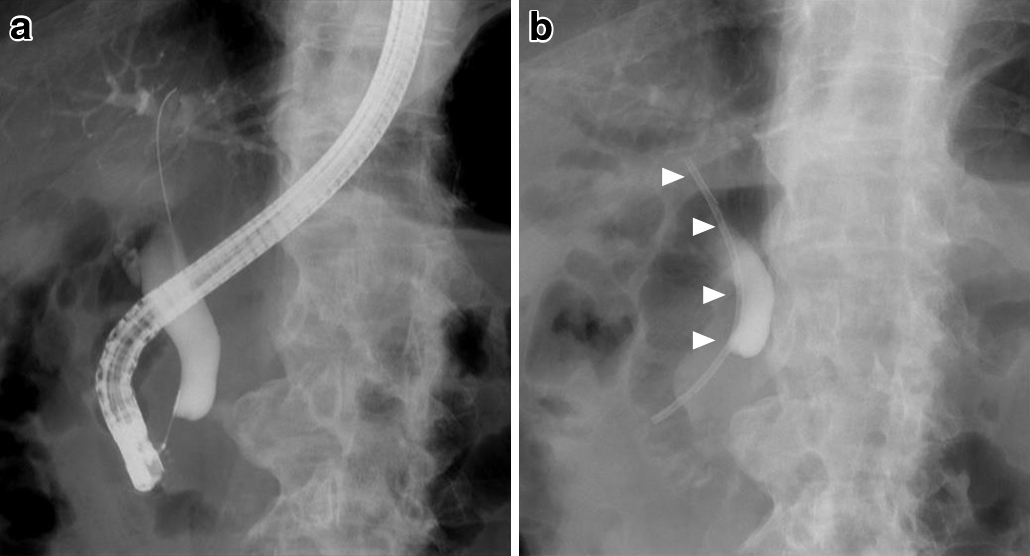

ERCPでは下部胆管に狭窄(Fig. 1a)を認め,狭窄解除の目的に胆管ステントを挿入した(Fig. 1b).胆汁細胞診では悪性所見は認めなかった.

Endoscopic retrograde cholangiography (ERC). a: ERC examination showed lower bile duct stenosis. b: A biliary stent was placed into the lower bile duct (arrowheads).